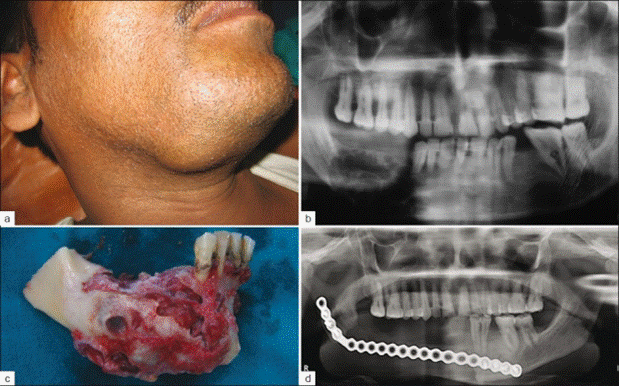

Theo chia sẻ từ Long Chun, sau buổi ghi hình số thứ 4 của chương trình, anh chàng đi khám và phát hiện bên xương hàm phải có một khối u khá lớn và nó đã ăn vào gần như hết vùng xương hàm bên phải. Ngay lập tức, Long Chun phải đặt vé máy bay trở về Hà Nội để kiểm tra chính xác tình trạng bệnh mà mình đang gặp phải. Kết luận cho thấy, Long Chun có một khối u nguy hiểm mang tên u men xương hàm. Nếu để lâu mà không điều trị ngay thì khối u có thể ăn vào máu và làm tăng nguy cơ mắc ung thư máu cao.

Để ý kỹ trong một vài tập Gương Mặt Thân Quen trước đó, phần má phải của Long Chun đã có hiện tượng sưng nhẹ.

U men răng cũng thường xảy ra ở đối tượng nam giới nhiều hơn. Khối u men răng có thể liên tục phát triển và xâm lấn một cách âm thầm. Sau một thời gian dài ủ bệnh, u men răng có thể biểu hiện ác tính, xâm lấn dần vào vùng xương hàm khiến cho phần má sưng đau, gây biến dạng mặt bất thường nếu u to lên.

- Ở giai đoạn u men phát triển: bạn có thể gặp phải một số vấn đề ở vùng xương hàm như tê môi cằm, sưng hàm, biến dạng mặt (khiến mặt lệch hẳn sang một bên), răng trên u có thể lung lay hoặc di lệch một ít kèm theo biểu hiện đau nhức, khó chịu và chảy mủ.

- Ở giai đoạn muộn: khối u lúc này đã đạt kích thước lớn, gây phồng xương nhiều nên làm mặt biến dạng rõ, xương bị phá hủy. Lúc này, bệnh nhân cũng cảm thấy đau nhức, răng lung lay nhiều và dễ bị xô lệch hơn.

1. Phẫu thuật cắt bỏ khối u: Khối u này thường phát triển ở vùng xương hàm nên bác sĩ sẽ phải cho tiếp cận phẫu thuật từ sớm để làm giảm nguy cơ tái phát u men răng.

2. Phẫu thuật sửa chữa hàm: Nếu phẫu thuật cắt bỏ u liên quan đến việc loại bỏ một phần xương hàm của bệnh nhân, bác sĩ có thể tiến hành một ca phẫu thuật khác để sửa chữa và tái tạo lại hàm. Điều này giúp cải thiện mặt thẩm mỹ và chức năng của hàm (hỗ trợ cho hoạt động ăn uống và nói chuyện).